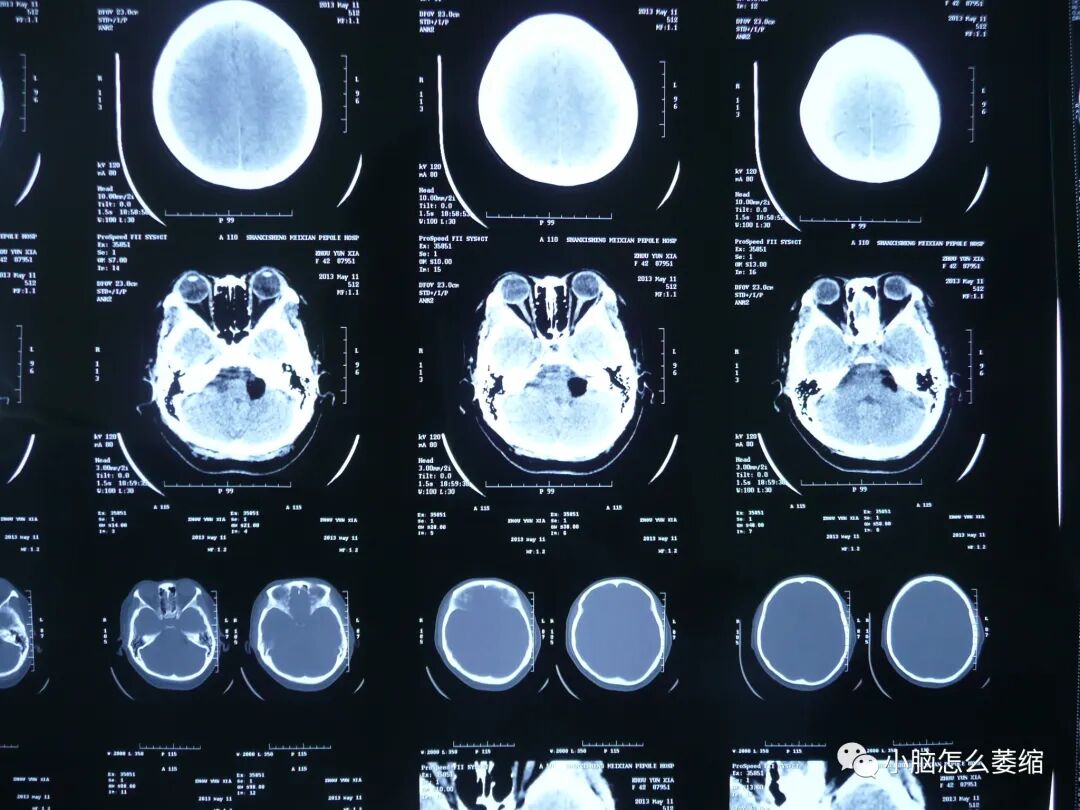

小脑萎缩是一种较为常见的神经系统疾病,患者常常出现平衡障碍、肌张力减退、言语不清等症状。近年来,越来越多的研究表明中药在治疗小脑萎缩方面具有一定的疗效。本文将介绍一例小脑萎缩患者接受中药治疗的情况。

患者张先生,男性,今年67岁。两年前,他被诊断出患有小脑萎缩。张先生主要表现为行走不稳、言语含糊不清、眼球震颤等症状。经过一系列西医治疗,效果并不明显。后来,他经朋友介绍找到了盛劲强大夫。